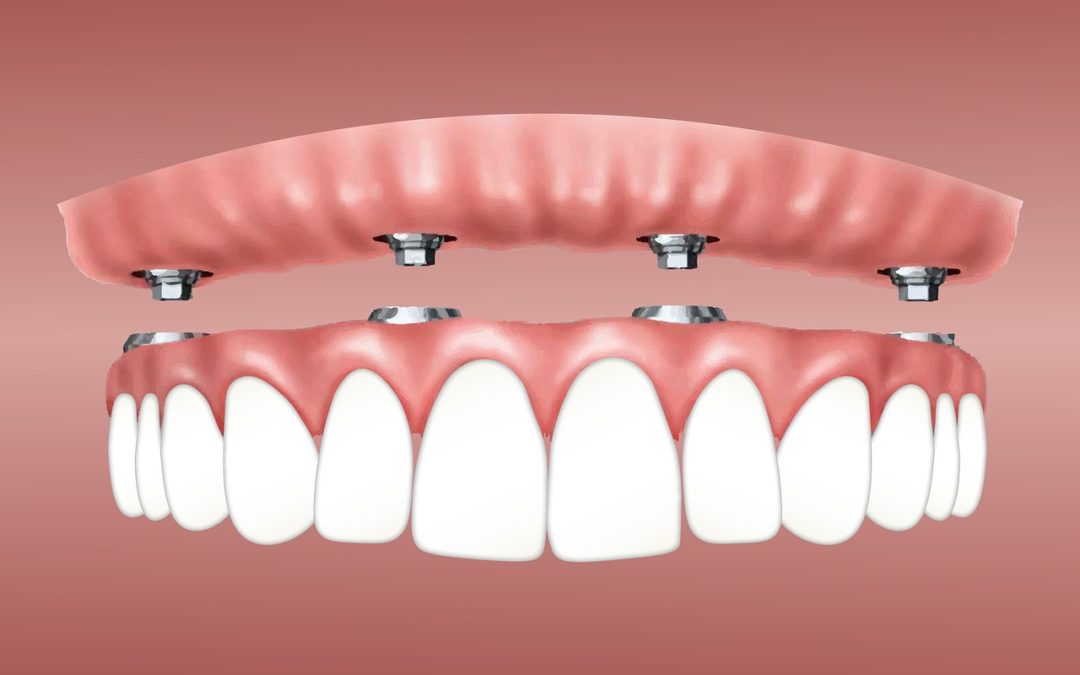

What Are Conventional Dental Implant Options?

In simple terms, dental implants are metal posts or frames that are surgically placed into the jawbone underneath your gums. Once in position, they give your local Rancho Cucamonga Dentist an opportunity to safely mount replacement teeth onto them. How Exactly Do They...

Getting A Better Understanding Of Dental Implants

Dental implants have have innovated the replacement of teeth. Before the development of dental implants, people with dentures were not able to chew a variety of foods; this has been revised with the widespread use of dental implants. According to the Dental Tribune,...

The Different Types Of Implants – Rancho Cucamonga Dentist

Basically, dental implants are metal articles or frames that are surgically placed into the jawbone underneath your own teeth. Once in position, they supply your local Rancho Cucamonga Dentist an opportunity to safely mount replacement teeth on them. Rancho Cucamonga...